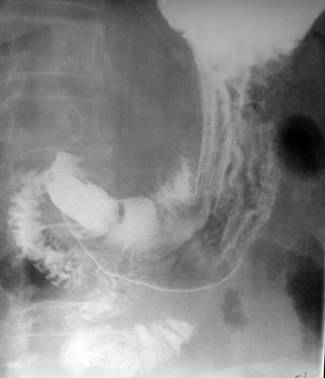

In cadrul limfomului gastric primitiv examenul radiologic gastroduodenal constituie de obicei o prima etapa diagnostica atat datorita simptomatologiei bolnavului cat si datorita faptului ca este un mijloc de diagnostic simplu, neinvaziv si la indemana clinicianului. Examenul poate orienta de la inceput diagnosticul, poate influenta deciziile si specificitatea investigatiilor ulterioare, poate orienta spre un eventual examen endoscopic si nu in ultimul rand poate stabili contraindicatiile endoscopiei.

Radiografia reprezinta o metoda de analiza foarte accesibila si a stomacului si un document de evolutie a bolii. Explorarea esofagului, stomacului si doudenului se face de rutina concomitent, cu administrare de contrast per os si poarta numele de examen eso-gastro-duodenal. Cea mai folosita substanta de contrast este sulfatul de bariu chimic pur, substanta neutra din punct de vedere fizic si chimic care nu reactioneaza cu mediile cu pH diferit si care are in compozitie bariu cu numar atomic mare deci in concluzie cu absortie mare pentru fasciculul de raze X. Sulfatul de bariu este o substanta insolubila cu apa, insipida si inodora. Este utilizat sub forma de pulbere ale carei particule trebuie sa fie suficient de mici pentru a face o buna dispersie in apa. Suspensia obtinuta trebuie sa fie cat mai omogena si mai aderenta la tubul digestiv. Pentru cresterea aderentei se pot adauga agenti chimici de omogenizare. In general suspenia de sulfat de bariu nu are contraindicatii dar cand se suspicioneaza existenta unei fistule in peretele tubului digestiv ce poate comunica cu cavitatea peritoneala sau se suspicioneaza un sindrom ocluziv este contraindicata folosirea substantelor de contrast iodate.(Radiologie si imagistica medicala, Constantin Zaharia, S.A. Georgescu).

La nivelul abdomenului, modificarile radiologice sunt aceleasi cautate in orice suspiciune de neoplazie cu localizare gastrica. Exista unele caracteristici specifice. Examenul radiologic standard analizeaza lacunele (numarul, localizarea, dimensiunile si conturul lor), ulceratiile (numarul, localizarea, dimensiunile si conturul lor), starea pliurilor (normale, ingrosate, dezordonate sau intrerupte), infiltratiile, modificarile de tonus si peristaltica si autoplastica prezenta sau absenta.

Formatiunile dezvoltate endolumenal sunt reprezentate prin lacune, care se traduc in semiologia radiologica ca imaginile unor formatiuni protruzive, de origine inflamatorie sau tumorala, in lumenul unui segment de tub digestiv. Cand sunt localizate intralumenal nu altereaza integritatea conturului lumenului, iar cand sunt periferice afecteaza conturul lumenului. Pot fi unice sau multiple, cu contur bine precizat sau nu, regulat sau nu, posibil sters partial. Forma poate fi rotunda, ovalara sau neregulata. La periferie pot prezenta zone de semiton. Dimensiunile lacunelor reproduc de multe ori dimensiunile tumorei maligne, iar caracteristic sunt unice (rar multiple), de obicei marginale, prezentand imagini de semiton la periferie, iar racordul cu conturul lumenului este afectat de existenta pintenilor maligni. Pliurile mucoasei pot fi impinse, intrerupte, ingrosate si neregulate. Nu in ultimul rand pot prezenta ulceratii. Acestea din urma traduc existenta unor solutii de continuitate la nivelul suprafetelor mucoasei, respectiv a masei tumorale. De obicei nisele sunt incastrate (nu proemina din conturul gastric), suprafata este mai tot timpul mai mare decat adancimea, au pliuri intrerupte in jurul lor, in incindenta ortograda sunt situate in interiorul lacunelor, versantii sunt neregulati, iar portiunea decliva are conturul sters.

O alta modificare radiologica importanta care traduce infiltrarea mucoasei este rigiditatea. Aceasta se insoteste de obicei de abolirea peristalticii. Radiologic apare o portiune de contur cu aspect rectiliniu si dimensiuni variabile ce poate afecta conturul in intregime. La modificarea pozitiei nu se modifica aspectul regiunii, dar poate duce la modificarea formei stomacului.

Lacunele si ulceratiile duc si la modificarii ale pliurilor care pot fi : ingrosarea lor, alterarea dispozitiei normale, intreruperea sau stergerea lor. Autoplastica de mucoasa este un semn de importanta majora care reprezinta infiltrarea muscularei mucoasei si de multe ori constituie un semn premonitor. Desi apar tardiv, hipootoniile gastrice, mult mai frecvente decat hipertoniile, sunt insotite frecvent de staza. De obicei aceste modificari de peristaltica sunt corelate cu aparitia rigiditatii.

La nivelul stomacului CT analizeaza peretele ingrosat segmentar sau difuz, prezenta ulceratiilor, existenta adenopatiilor (supra sau infradiafragmatice), dar si existenta altor leziuni limfomatoase de organ (ficat, splina, pancreas, rinichi, suprarenala). Astfel CT este singura explorare care deceleaza ingrosarea peretelui gastric, care poate fi segmentara, cand afecteaza doar o anumita portiune, sau poate fi extinsa cand afecteaza intreg peretele gastric. Un avantaj major al CT este acela ca poate furniza concomitent date importante asupra extensiei procesului tumoral in spatiul perigastric. Astfel CT depisteaza si stadilizeaza tumorile de tub digestiv, monitorireaza postterapeutica acestora si depisteaza existenta patologiilor asociate. Dar, datorita complexitatii si fiabilitatii sale, dar si a pretului de cost mult mai ridicat este considerata totusi o metoda complementara radiografiei standard.

CT este o etapa complementara si succesiva examenului radiologic gastro-duodenal care confirma si evalueaza leziunile descoperite prin mijloace radiologice standard. Pe langa faptul ca apreciaza cu exactitate ingrosarile de perete gastric, este singura metoda radiologica ce poate pune in evidenta depasirea seroasei si invazia spatiului perigastric de catre limfom. Prin posibilitatea efectuarii punctiei bioptice, CT ofera diagnosticul histologic de limfom.